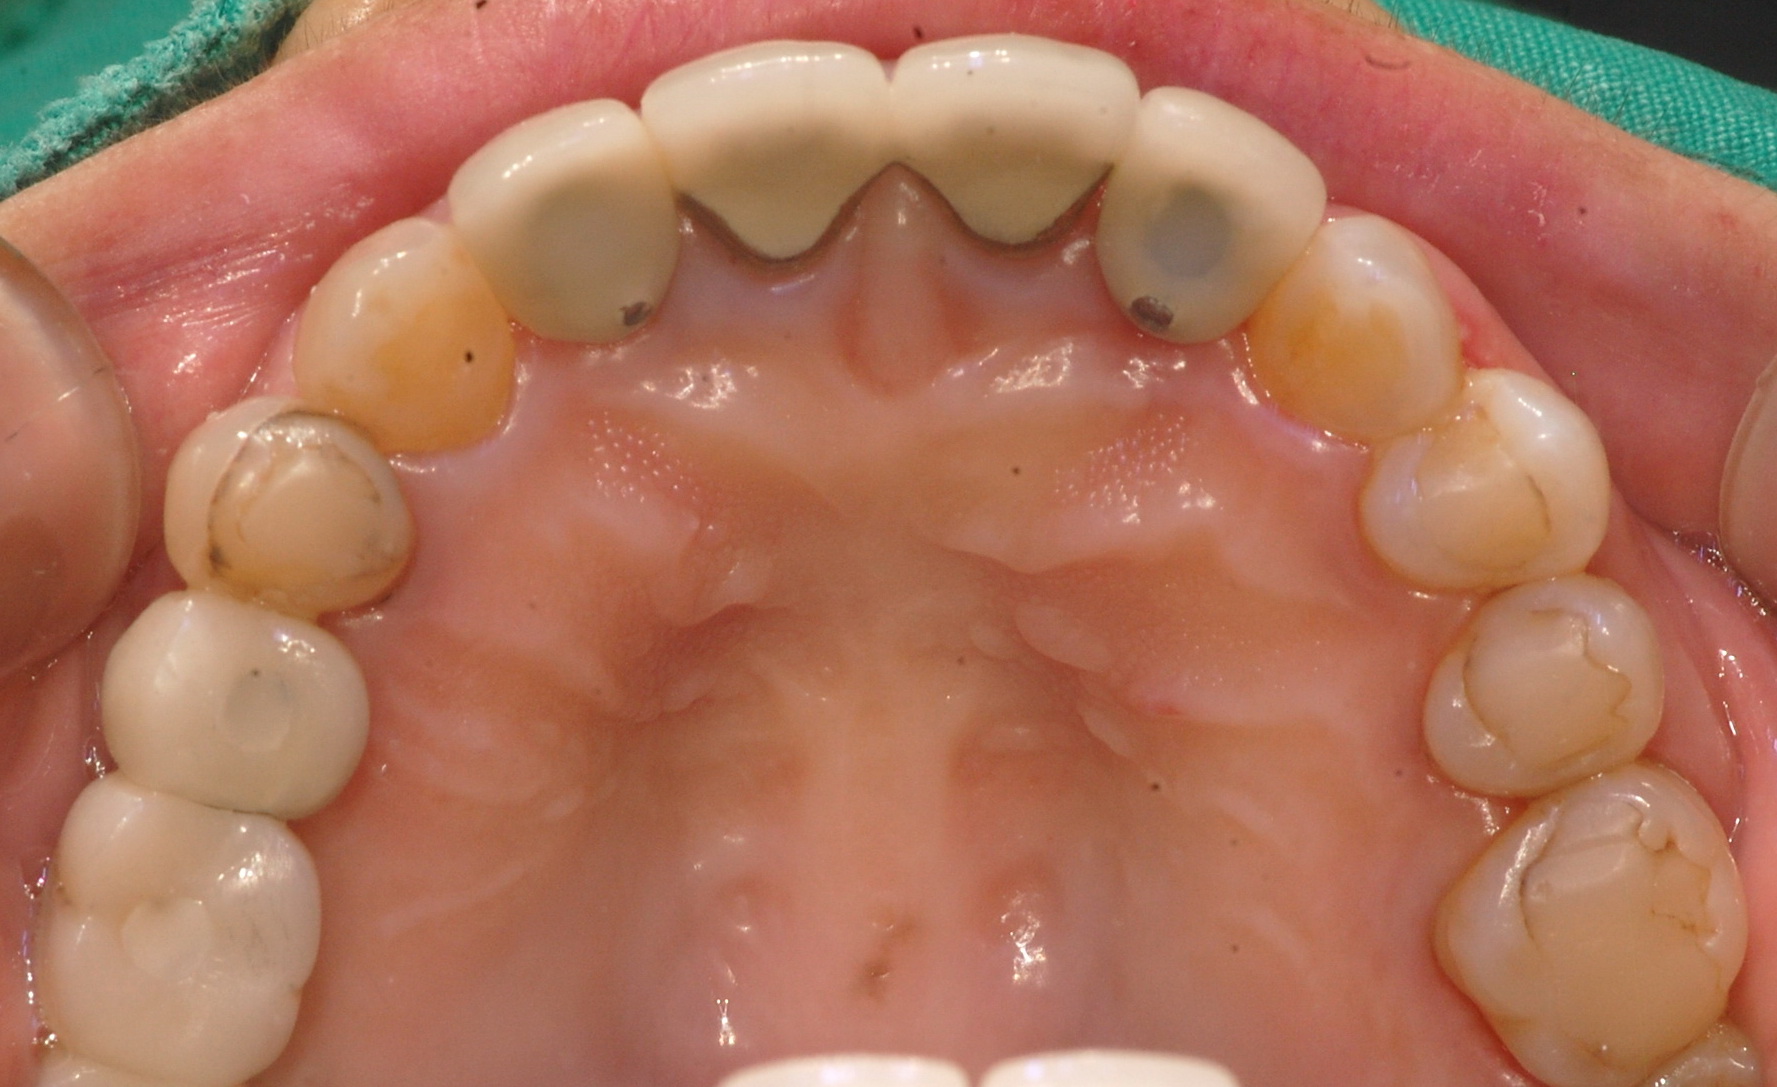

[임플란트] 제목 : 임플란트 PFM 보철

임플란트 PFM 보철